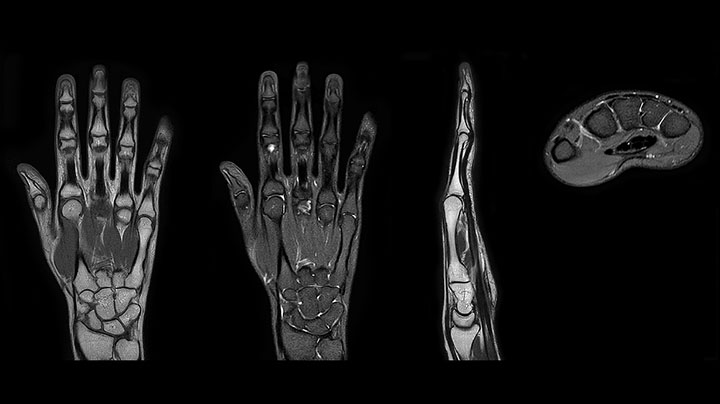

Positioning and operation: smooth and simple Once the scanner was in place, Mrs. Schiffer and her staff received tailored training in line with their clinical and workflow requirements and objectives. “I have been impressed from the start. Installation and set-up were smooth and simple. Within three days, our technologists were confidently using the new system,” recalls Mrs. Schiffer. Since installing Prodiva 1.5T, she and her team have noticed a number of enhancements to their daily work. The scanner’s simple Breeze workflow supports easy patient positioning with fewer positioning steps, rapid set-up and changeover times. Ultra-light anterior coils, short cables and small connectors are making technologists’ lives easier. Senior MRI technologist Sandra Maass says: “Speaking for myself and my colleagues, we all very much enjoy using Prodiva – and we benefit from its many workflow advantages every day.” And Mrs. Schiffer adds, “The flexible, lightweight coils fit really well to the patient’s body shape, and the connectors are superb: connecting and disconnecting requires just little effort.” “The shoulder coil is a great example of easy positioning with Prodiva,” says Mrs. Maass “Other shoulder coils can be quite rigid, so that patients with pain, or bigger stronger shoulders, or a somewhat abnormal shoulder or spine anatomy cannot be positioned well in the coil, which often leads to loss of image quality. However, the Prodiva shoulder coil is very flexible and has large coverage, which makes good positioning easier and that contributes to the superb image quality and high SNR that we get in our shoulder exams.” High quality of images impresses From a clinical perspective, too, Mrs. Schiffer is very impressed with Prodiva 1.5T. In her practice around 50% of scans are neurological, 40% musculoskeletal and the rest made up of vascular, abdominal and miscellaneous cases. The radiology team is receiving good results across anatomies, which their referring physicians are confirming to them. “Prodiva’s high image quality and advanced features, including diffusion-weighted imaging in many organs, improve our diagnostic confidence and help decision-making,” says Mrs. Schiffer. “Prodiva has been an excellent investment and is definitely the right choice for us.” “The quality of the contrast-free MR angiography keeps impressing us,” says Mrs. Schiffer. “In addition to not having to inject contrast agent, these images are amazing, for instance of the carotids. Also our exams of shoulders and hands are really exceptional. Images of the hands, for example, cover the fingertips and include the full wrist as well, all with high signal-to-noise ratio.”

Prodiva imaging of the hand covers the fingertips and includes the full wrist as well. The dS MSK M coil is easy to use.

Scan time 4:19 min, FOV 160 mm, acq voxels 0.55 x 0.80 x 3.0 mm.

Scan time 2:50 min, FOV 160 mm, acq voxels 0.70 x 0.99 x 3.0 mm.